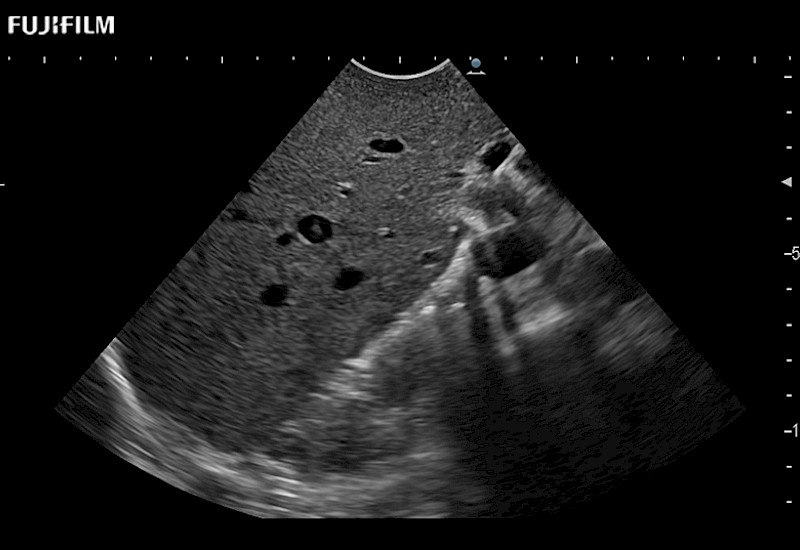

The ARIETTA 750 incorporates all of the proven technologies and functions that medical professionals have come to expect from Fujifilm Healthcare.

ARIETTA 750 is the definitive diagnostic ultrasound solution for any clinical setting - Private Office, Imaging Center, or Hospital. The ARIETTA platform provides the ultimate in clinical performance with its state-of-the-art features and large user-friendly display.

The ARIETTA 650 DI combines trusted Fujifilm Healthcare technologies and features tailored for surgical oncology.

Designed to meet the demands of surgeons, the ARIETTA 650 DI offers precise guidance. Its advanced capabilities and large, intuitive display offer accurate and efficient care in operating rooms and specialized surgical settings.